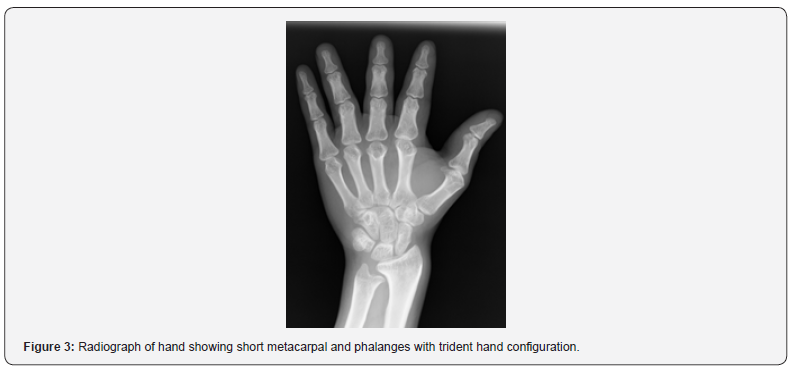

Achondroplasia is the most frequent form of short - limb dwarfism [1]. The phenotype is characterized by rhizomelic disproportionate short stature, enlarged head, midface hypoplasia, short hands and lordotic lumbar spine [2,3]. Its incidence is 1 in 10,000 to 1 in 30,000 [1]. Here we describe a case of achondroplasia in a 37-year-old male, who presented to endocrinology OPD for short stature. General physical examination showed large head, depressed nasal bridge short stature, with rhizomelic shortening of the arms and legs and normal trunk length (Figure 1). Patient had short, stubby fingers and excessive spacing between third and fourth finger (Figure 2). Anthropometry revealed a height of 115.5 cm (midparental height - 155.2 cm), weight of 41.4 kg. His vital signs were within the normal limits. Systemic examination did not reveal any abnormality. Hand‑wrist radiograph showed short metacarpal and phalanges with trident hand configuration (Figure 3). X ray of lower limb reveled short and thick tubular long bones (Figure 4). Based on clinical examination and radiological features; diagnosis of achondroplasia was confirmed.